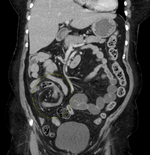

| Coronal CT of the abdomen, demonstrating a volvulus as indicated by twisting of the bowel stock | |

CT scan of a small bowel volvulus. It shows two juxtaposed segments of narrowing, which is the spot of mesentery rotation. The other signs indicate strangulation.